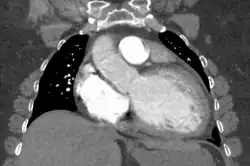

Diagnosis

Generalized enlargement of the heart is seen upon normal chest X-ray. Pleural effusion may also be noticed, which is due to pulmonary venous hypertension.[28]

The electrocardiogram often shows sinus tachycardia or atrial fibrillation, ventricular arrhythmias, left atrial enlargement, and sometimes intraventricular conduction defects and low voltage. When left bundle-branch block (LBBB) is accompanied by right axis deviation (RAD), the rare combination is considered to be highly suggestive of dilated or congestive cardiomyopathy.[29][30] Echocardiogram shows left ventricular dilatation with normal or thinned walls and reduced ejection fraction. Cardiac catheterization and coronary angiography are often performed to exclude ischemic heart disease.[28]

Cardiac magnetic resonance imaging (cardiac MRI) may also provide helpful diagnostic information in patients with dilated cardiomyopathy.[32]